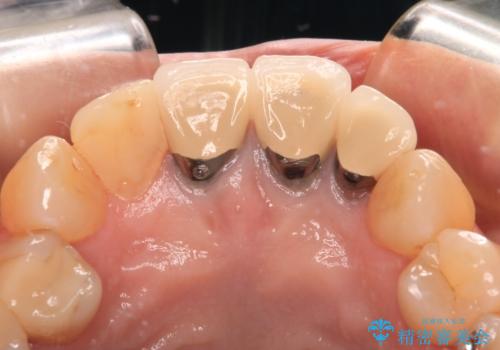

- 黄色みのある前歯のセラミックを、明るい色に替えたいとのことで来院された患者様です。

透明感がないことも気になっていたため、オールセラミッククラウンでは透けてしまう可能性のある金属の土台をファイバーコアに置き換え、1トーン明るいクラウンにて仕上げていくこととしました。